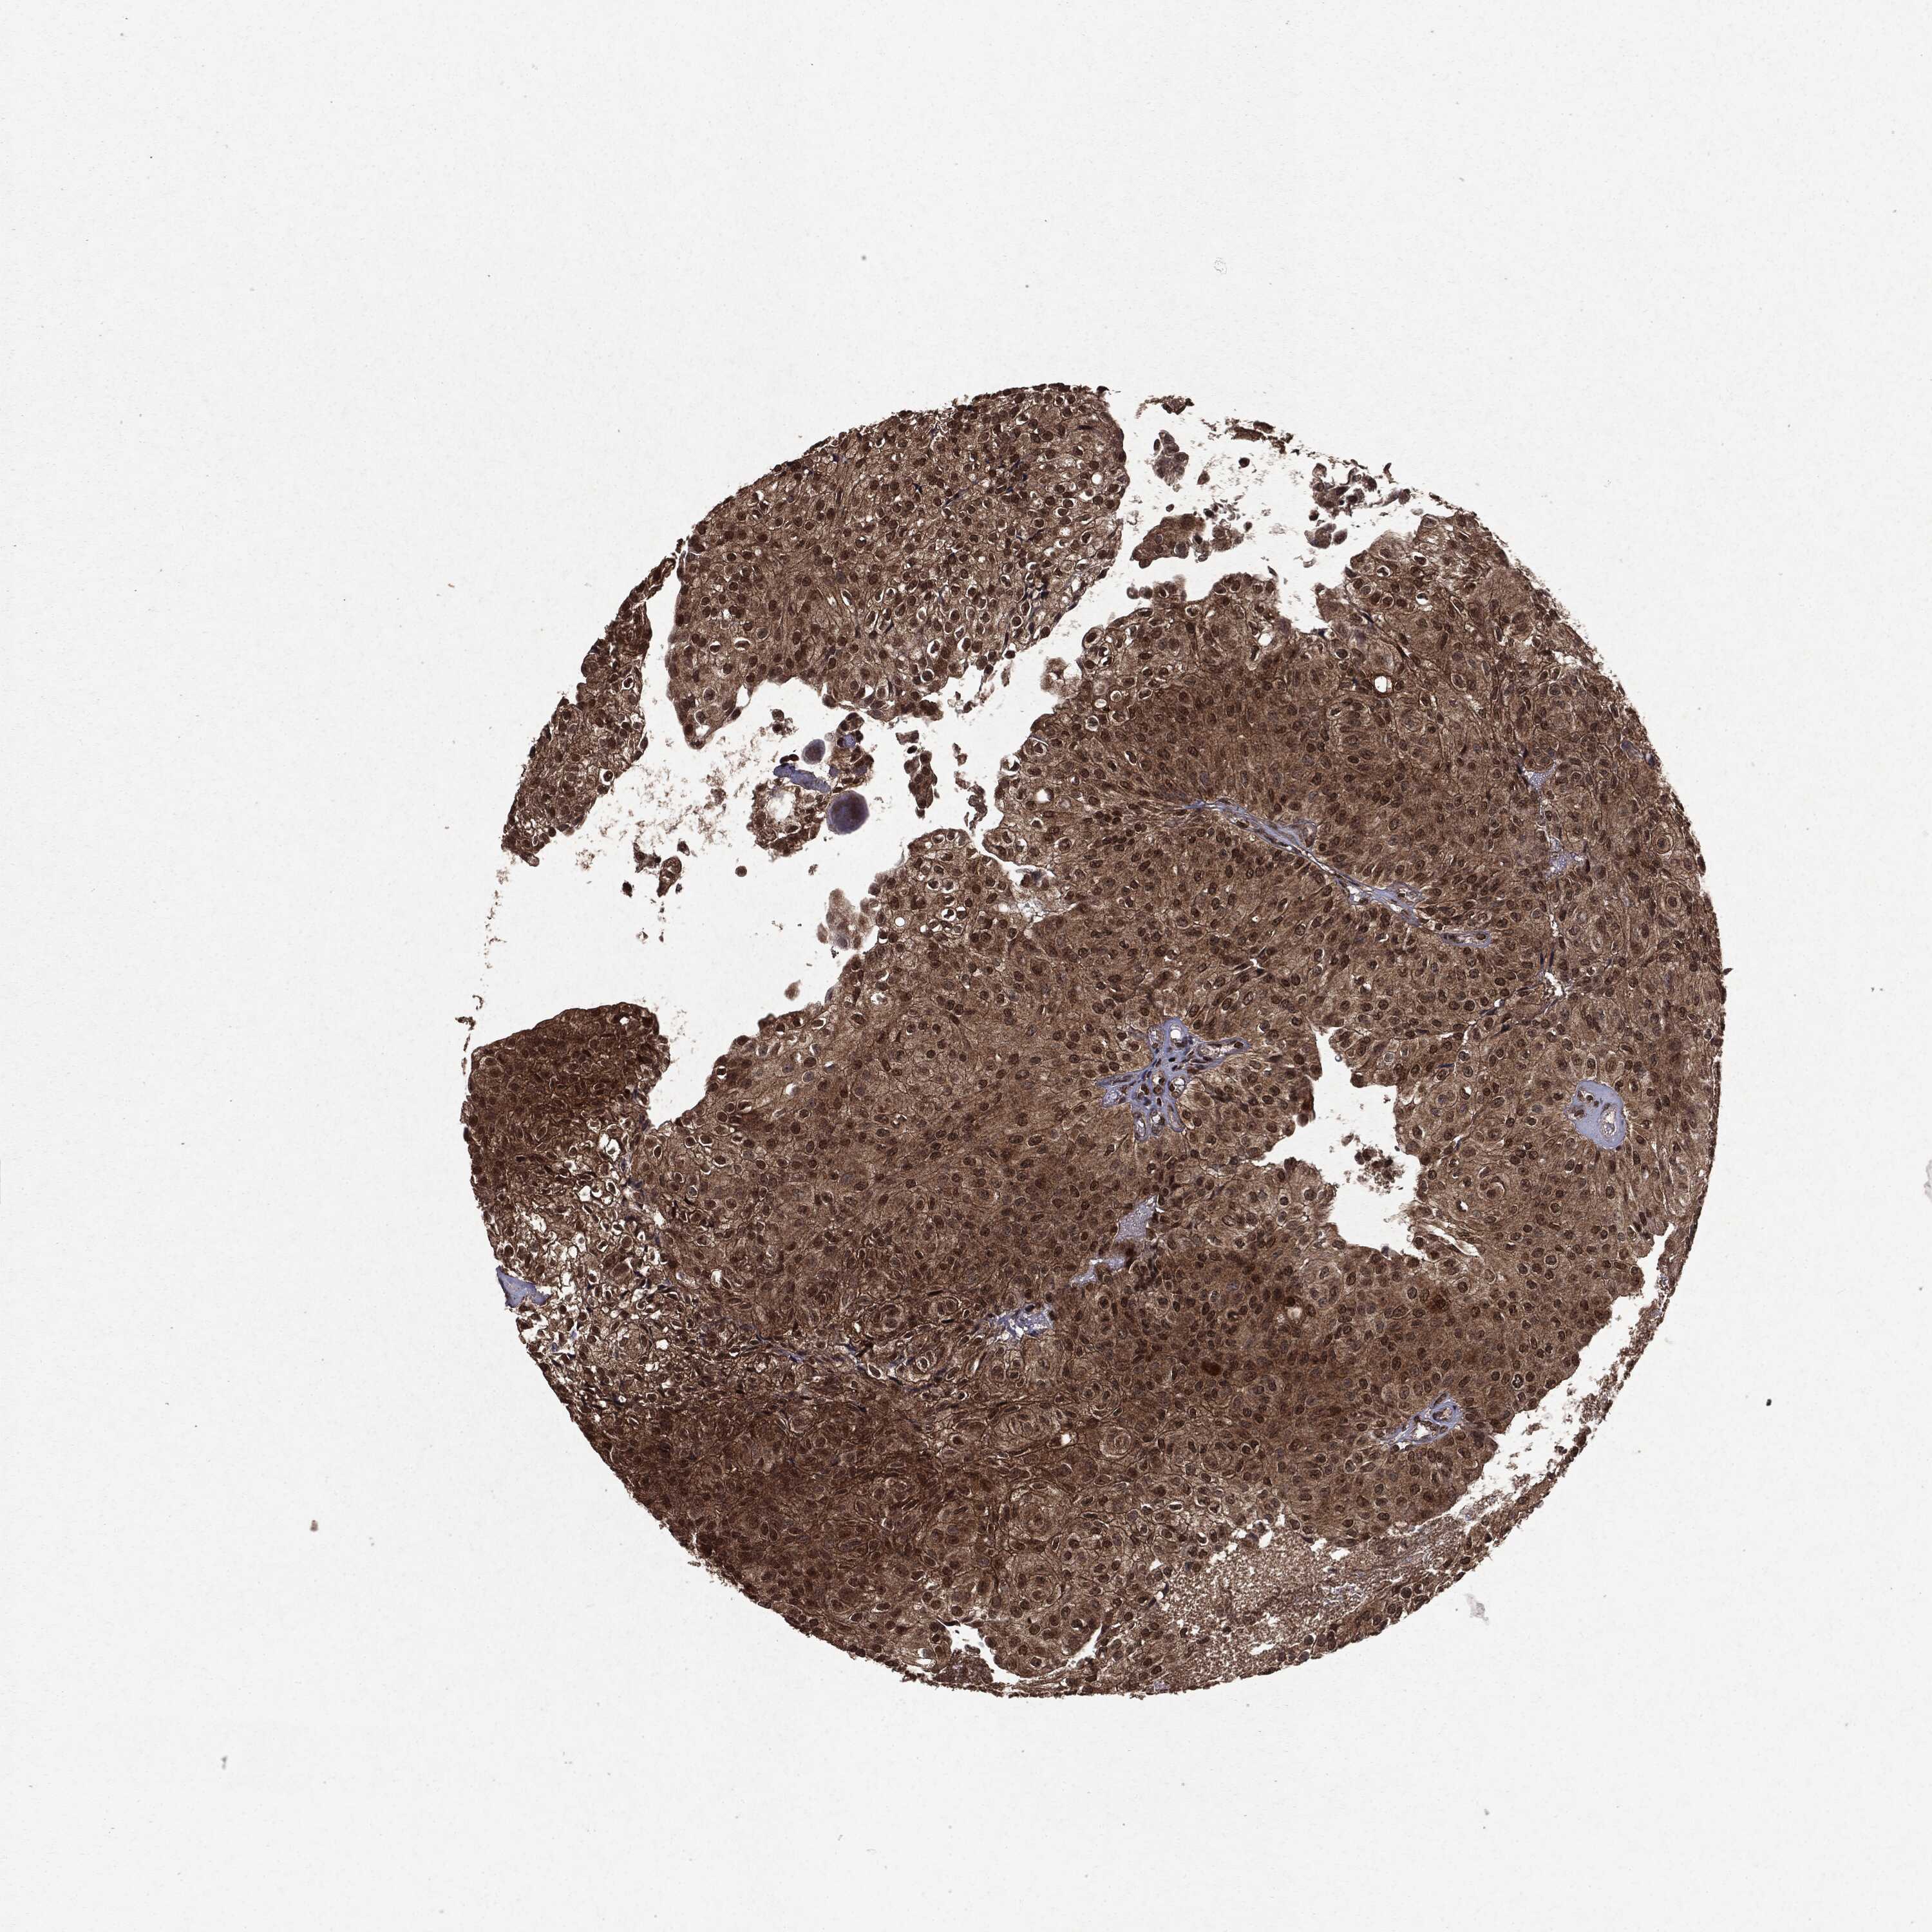

UROTHELIAL CANCER - Protein expressioni

A mouse-over function shows sample information and annotation data. Click on an image to view it in a full screen mode. Samples can be filtered based on level of antibody staining by selecting one or several of the following categories: high, medium, low and not detected. The assay and annotation is described here.

Note that samples used for immunohistochemistry by the Human Protein Atlas do not correspond to samples in the TCGA dataset.

Antibody stainingi

Antibody staining in the annotated cell types in the current human tissue is reported as not detected, low, medium, or high, based on conventional immunohistochemistry profiling in selected tissues. This score is based on the combination of the staining intensity and fraction of stained cells.

Each image is clickable and will lead to virtual microscopy that enables deeper exploration of all samples and also displays staining intensity scores, fraction scores and subcellular localization as well as patient and tissue information for each sample.

Antibody HPA008819

Urothelial carcinoma, High grade